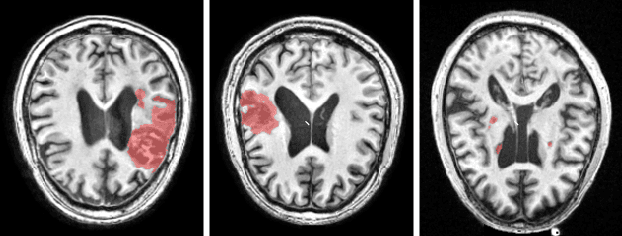

There are considerable interests in automatic stroke lesion segmentation on magnetic resonance (MR) images in the medical imaging field, as strokes are the main cause of various cerebrovascular diseases. Although deep learning-based models have been proposed for this task, generalizing these models to unseen sites is difficult due to not only the large intersite discrepancy among different scanners, imaging protocols, and populations but also the variations in stroke lesion shape, size, and location. Thus, we propose a U-net--based segmentation network termed SG-Net to improve unseen site generalization for stroke lesion segmentation on MR images. Specifically, we first propose masked adaptive instance normalization (MAIN) to minimize intersite discrepancies, standardizing input MR images from different sites into a site-unrelated style by dynamically learning affine parameters from the input. Then, we leverage a gradient reversal layer to force the U-net encoder to learn site-invariant representation, which further improves the model generalization in conjunction with MAIN. Finally, inspired by the "pseudosymmetry" of the human brain, we introduce a simple, yet effective data augmentation technique that can be embedded within SG-Net to double the sample size while halving memory consumption. As a result, stroke lesions from the whole brain can be easily identified within a hemisphere, improving the simplicity of training. Experimental results on the benchmark Anatomical Tracings of Lesions After Stroke (ATLAS) dataset, which includes MR images from 9 different sites, demonstrate that under the "leave-one-site-out" setting, the proposed SG-Net substantially outperforms recently published methods in terms of quantitative metrics and qualitative comparisons.